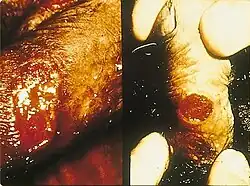

Granuloma inguinal ou donovanose é uma infecção sexualmente transmissível ocasionada pela bactéria gram-negativa Klebsiella granulomatis (anteriormente denominada Donovania graulomatis e posteriormente Calymmatobacterium granulomatis). Caracteriza-se pela presença de úlceras genitais.[1]

Após a inoculação, desenvolvem-se um ou mais granulomas subcutâneos indolores, que aumentam de tamanho e necrosam, levando a úlceras indolores, de base limpa e bordas bem demarcadas que podem sangrar. Pode afetar um ou mais gânglios linfáticos inguinais.[2]